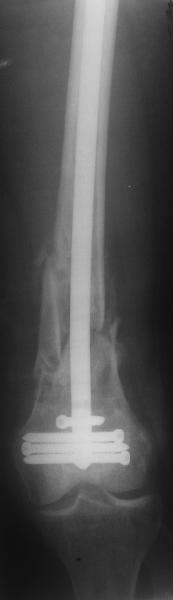

По прямой проекции неплохо. Что за стержень?

Антеградный остеосинтез при дистальных переломах бедра мы применяем давно, этот материал обобщен в канд. диссертации Александра Виноградского.

Алекс, как Вы можете говорить, что "по прямой проекции неплохо"!? :( Гвоздь в суставе !!!

Снимаю свои претензии. На втором из снимков, которыми Вы хвастаетесь, гвоздь тоже в суставе, и ничего :(

И вообще мне кажется, что представленный ОС не допустим:1. стержень в суставе,2. неправильная длинна винтов, 3. ось конечности неправильная, 4. циркулярная гипсовая повязка после ОС?????

-1. стержень в суставе,

Это не критично, в межмышелковой борозде,не на опроной поверхности, выступает из субхондральной кости, не факт что из хряща.Про надколенник Александр Николаевич уже писал.

-2. неправильная длинна винтов,

и толщина тоже. При такой длине хочется помощнее.

-3. ось конечности неправильная,

Вполне прилично. Если в боковой проекции рекувации нет. Где кстати боковая, хочется спросить у постмейкера.

- 4. циркулярная гипсовая повязка после ОС?????

К сожалению, автор умалчивает. Думается, что в данном случае можно и без гипса.

Приносим извенения за недостаток информации. Выкладываю все снимки. Стержень фирмы НПО ДЕОСТ(г.Пущино-на-оке)

Это результат через полгода. К сожалению, пациент больше не приезжал на контрольный осмотр.